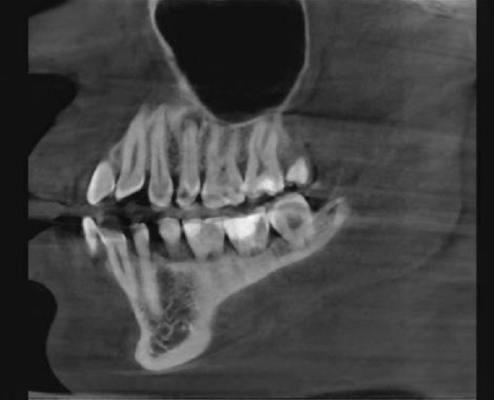

Фронтальная панорама (совмещение нескольких снимков). Прямоугольник — имплантат, его металл отражает излучение, но здесь включён постобработчик, который компенсирует гало-эффект. В овале зуб с пролеченными каналами, в каналах контрастный материал. Стрелка — зуб с живым нервом и пульпой.

Металлы, соответственно, дают очаги затемнения, как видите.